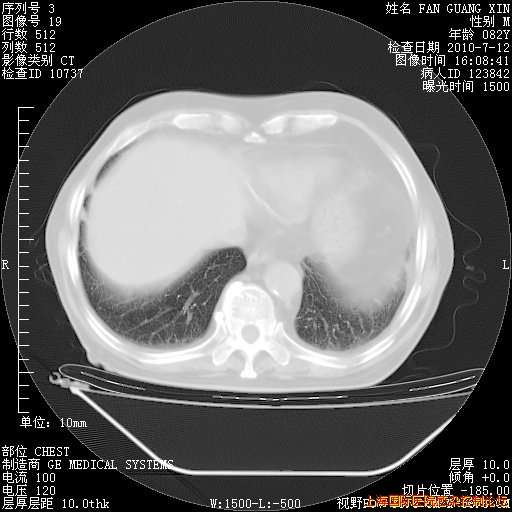

补发6月12日肺部CT肺窗

6月12日肺窗

整整相隔30天的肺部CT好像有所好转啊。甲强龙减量第3天,需要观察体温。

海管,自昨日你和我通完话后,不知您岳父消化道症状有无缓解?体温怎样?阅读7.12日胸部ct,个人认为目前激素治疗是有效的,甲强龙减量是适宜的。因在抗痨治疗,需密切观察肝功、肾功能和血常规。不过,老年、长期住院和大量使用激素,很担心菌群失调发生